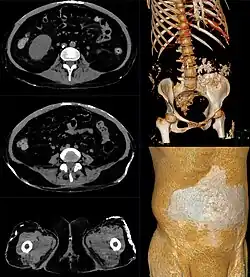

Eine gutartige, sehr seltene Kalzinose unklarer Ursache ist die Lipokalzinogranulomatose (auch tumoröse Kalzinose oder Morbus Teutschländer), bei der es in den Weichteilen in unmittelbarer Nachbarschaft der großen Gelenke zu einem langsamen Wachstum von verkalkten Tumoren kommt. Die Ursache sind Mutationen in den Genen für GALNT3, FGF23 oder KLOTHO.[1] Betroffen hiervon sind hauptsächlich Schwarzafrikaner bis zum 20. Lebensjahr.

- Pain in the Buttock in a Dialysis Patient. In: American Journal of Kidney Diseases. Vol. 52, Issue 4, 2008, Quiz Page October 2008, S. A45-A46, doi:10.1053/j.ajkd.2008.07.004 (englisch, Tumoröse Kalzinose, Kasuistik mit Bildern).